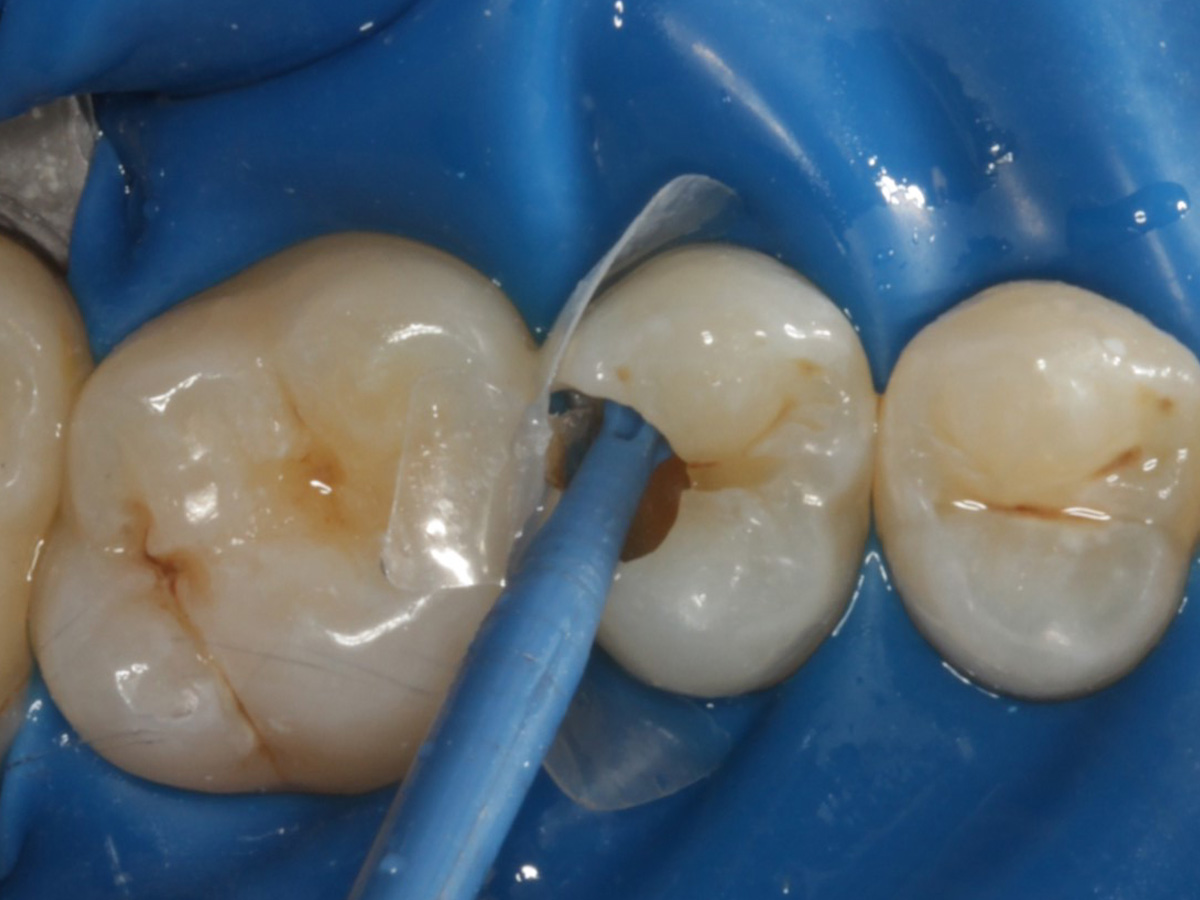

Abbildung 4

Schutz des Nachbarzahnes und des Kofferdams mit wiederverwandter Bioclear Biofit Matrize (gereinigt und sterilisiert); Separation zur Applikation der Matrize mit Heidemannspatel